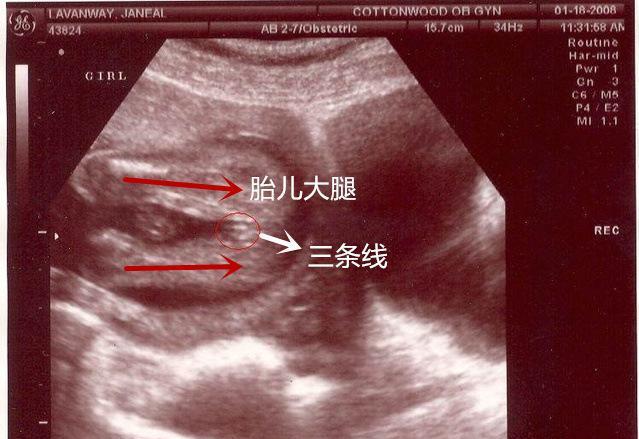

如团状东西,说明是男宝仔细看下图红圈里的三条线,这是很典型的女宝

给你看个图你就明白了…放大看两腿之间有三个点,三条白线,男宝是没有